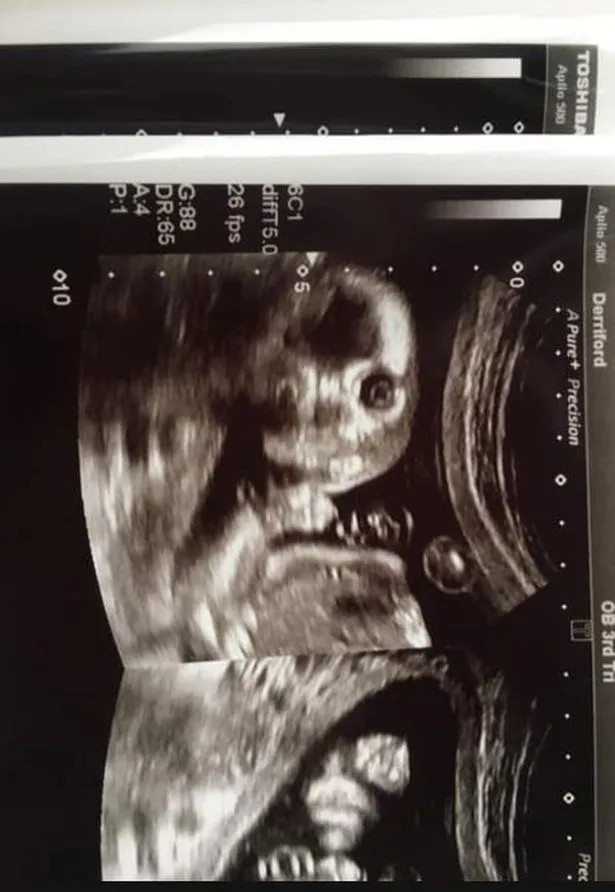

Jo az első rémület után a Facebookon is megosztotta az egyesek szerint sokkoló, de mindenképp meghökkentő képet.

A látvány még az angliai Derriford kórház tapasztalt alkalmazottját is mélyen megdöbbentette, állítása szerint ilyennel még nem találkozott a karrierje során.